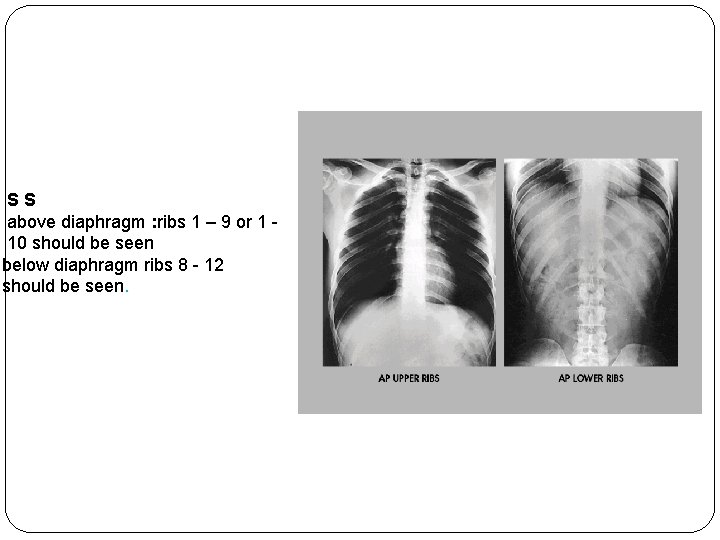

AP posterior ribs (upper and lower ribs) Film Size: 14 x 17 in. (35 x 43 cm). Crosswise or lengthwise. SHIELDING: Shield gonadal region. Patient Position: For upper ribs: Patient erect (preferred), specially in case of trauma to prevent lungs puncture by a fractured rib. For Lower ribs: Patient supine. Part Position: shoulders rotated interiorly to remove scapula away from the lung fields, Chin raised to prevent superimposition with upper ribs, patient looks straight ahead. Distance: 100 cm or 40 in, grid is used. k. V(65 – 75) for above diaphragm, (75 – 85) for below diaphragm. * C R: perpendicular to film. CP : Upper ribs (above diaphragm): To 3 or 4 in (8 – 10 cm ) below the jugular notch (level of T 7 ). Lower ribs (below diaphragm): Midway between hoid and lower rib cage. Collimation: collimate on four sides to area of interest For upper ribs: Exposure on the arrested full inspiration For lower ribs: Exposure on the arrested full expiration ( Basic)

SS above diaphragm : ribs 1 – 9 or 1 10 should be seen below diaphragm ribs 8 - 12 should be seen.